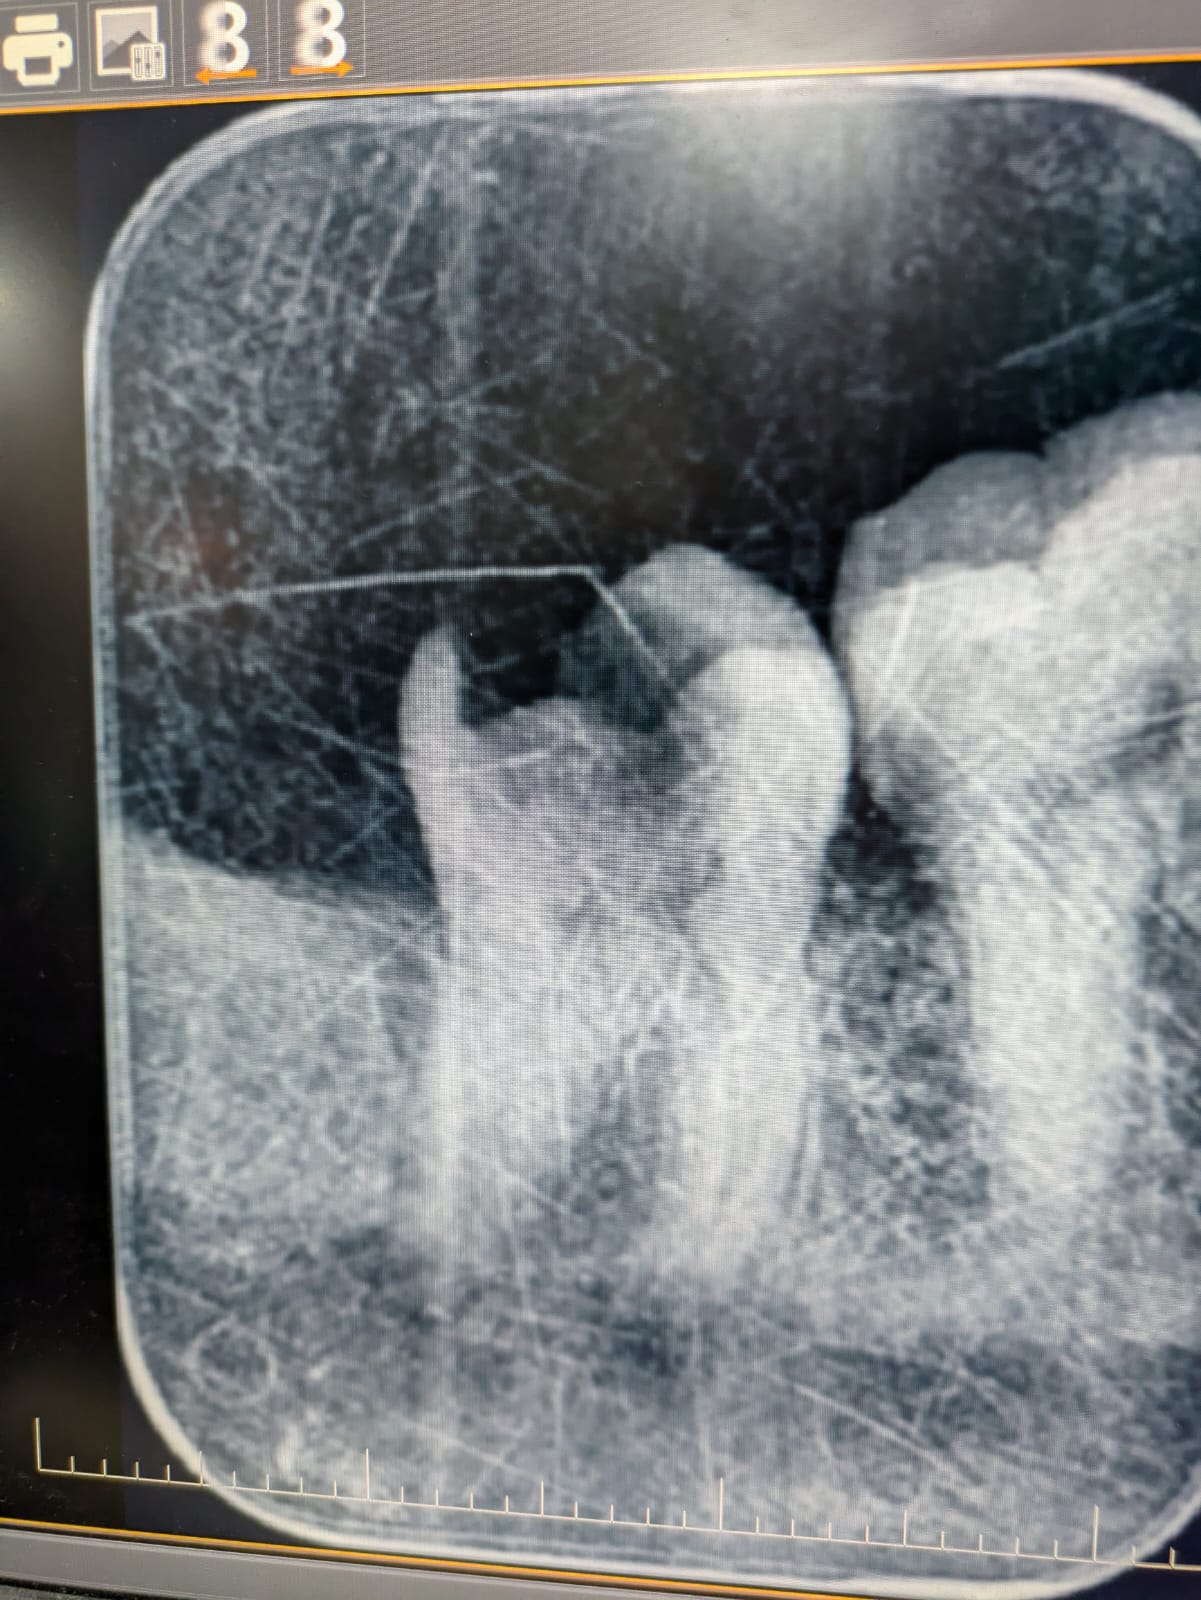

This radiograph is one of the clearest I have taken recently, and it highlights a tooth affected by decay. Let me explain it in simpler terms while also using some dental terminology for clarity.

In this image, you can see a tooth with visible decay on its top surface, known as the occlusal surface. The darker area visible in the radiograph represents the decayed portion, also called "radiolucency." This happens because decay, or caries, causes the tooth structure to break down, which appears as a dark shadow on an X-ray.

Inside every tooth, there’s a living part that consists of nerves and blood vessels. This central part is called the pulp. The pulp has two main sections: the coronal pulp, which is located in the crown (the visible part of the tooth), and the radicular pulp, which extends down into the roots. When decay progresses and gets very close to or reaches the pulp chamber, the tooth can become sensitive or even painful. At this stage, treatment is required to save the tooth.

If the decay is very close to the pulp but hasn’t entirely invaded it, dentists may perform a procedure called direct pulp capping. This involves placing a protective material over the pulp to seal it and prevent further infection. However, if the decay reaches the pulp chamber, the tooth becomes infected, and a root canal treatment (RCT) is necessary. In an RCT, the infected pulp is removed, and the space is cleaned, filled, and sealed to save the tooth from extraction.

Additionally, in this radiograph, you can observe an area of radiolucency around the tip of the tooth’s roots, called the periapical region. "Periapical" refers to the area surrounding the apex or tip of the root. This radiolucency is a sign that the infection has spread beyond the tooth into the bone around the root. This condition is often referred to as periapical pathology or a periapical abscess, and it typically occurs when the infection within the tooth has traveled down through the root canals into the surrounding tissues.

To summarize, this radiograph shows a tooth with advanced decay affecting its internal structures. While the decay has reached the pulp chamber and caused infection at the root tip, treatments like root canal therapy or pulp capping can help preserve the tooth and restore its function. This image serves as a great example of the importance of early detection and timely treatment to prevent complications.